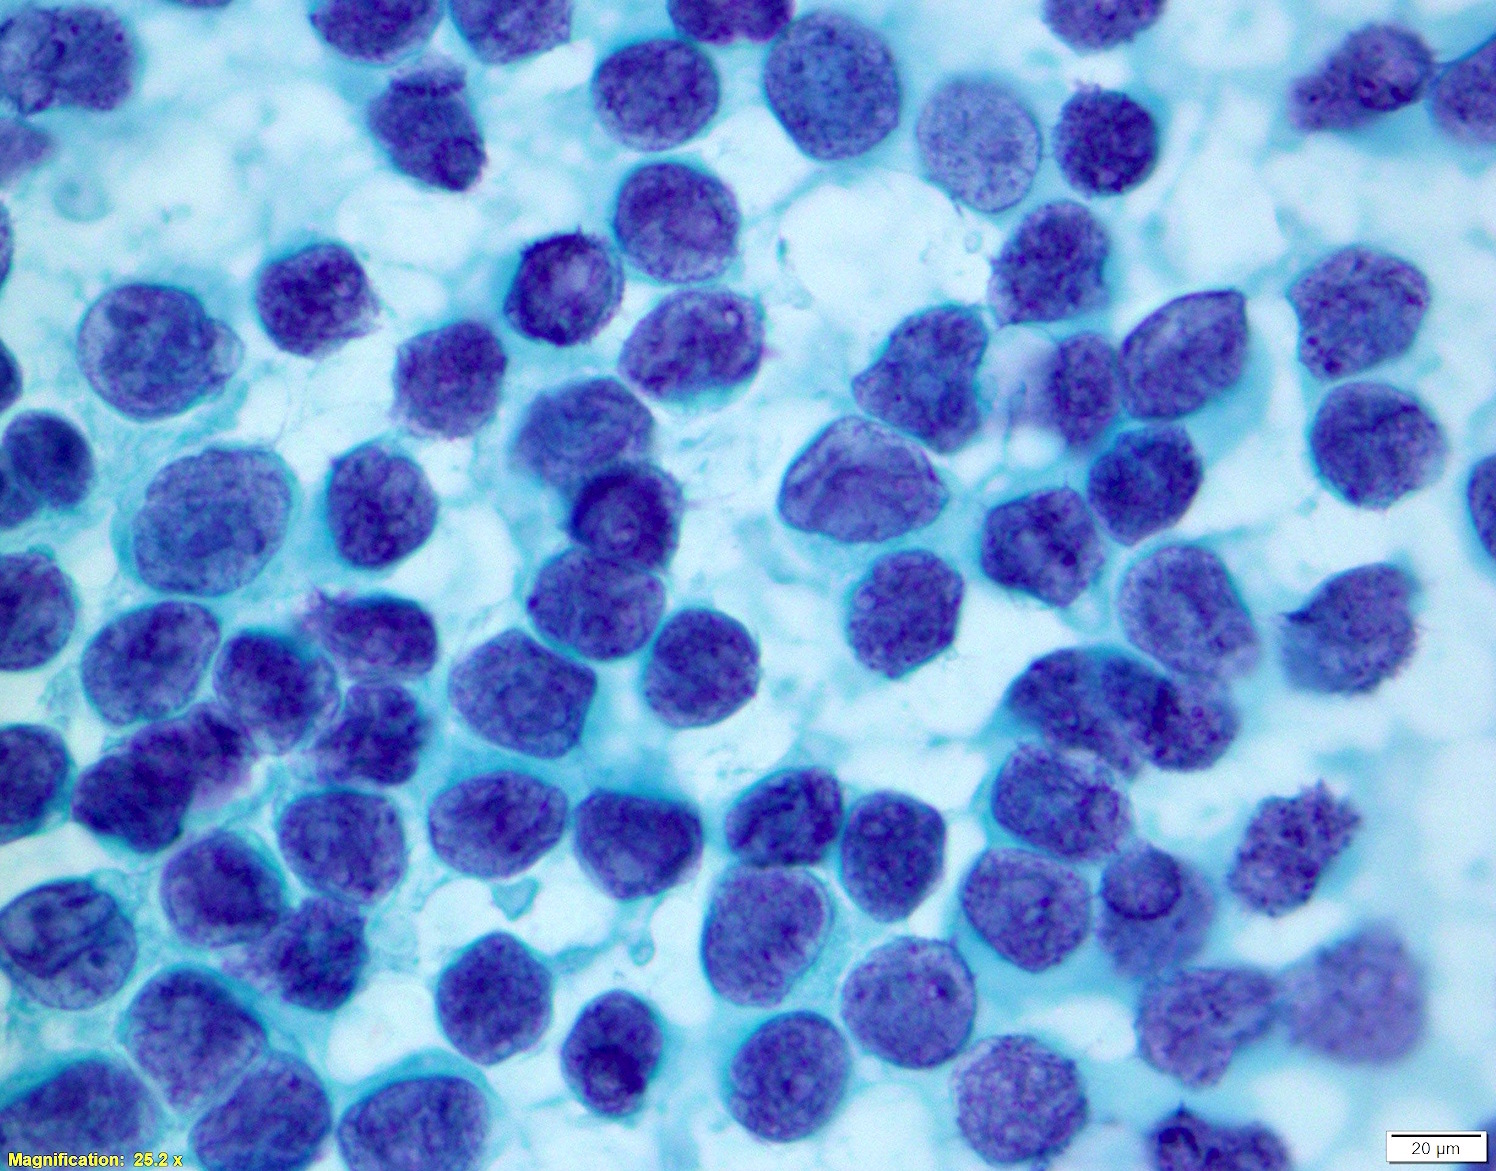

Cytology description

- Blastoid variant

- Monomorphic proliferation of intermediate sized to large lymphoid cells

- Round to oval nuclear contours

- Dispersed chromatin

- Small / inconspicuous nucleoli

- Scant, pale blue cytoplasm

- Pleomorphic variant

- Large, pleomorphic cells

- More nuclear irregularity

- More variation in size of cells

- Vesicular, open chromatin

- Prominent nucleoli often seen (Br J Haematol 1996;93:475)